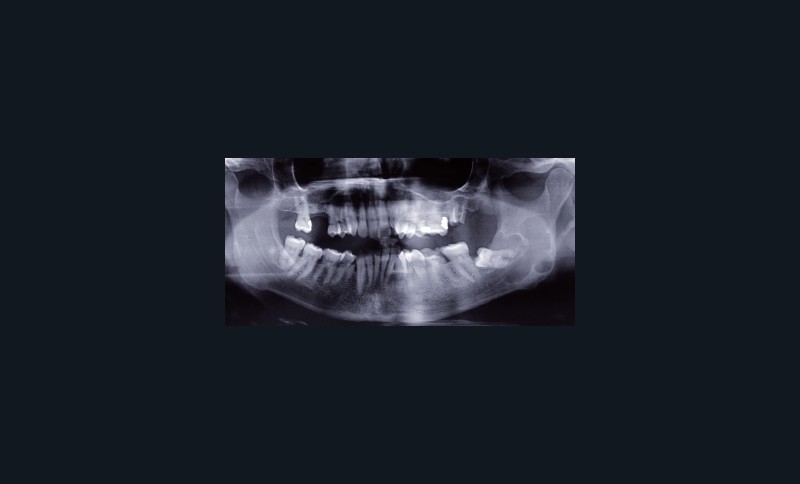

L’OPT est un outil de débrouillage indispensable pour tous les patients.

Sa lecture doit être systématique : état de la denture, structures osseuses environnantes, cavités aériques… Elle a l’avantage d’être bilatérale comparative.

Il faut également toujours comparer le cliché actuel aux clichés antérieurs pour évaluer l’évolution d’une lésion éventuelle de type granulome apical.